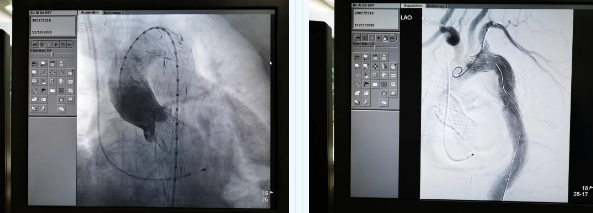

11月19日,西安國際醫(yī)學中心醫(yī)院心臟外科TAVR團隊在心臟病醫(yī)院張金洲副院長主持下,順利完成一例罕見“經(jīng)股經(jīng)導管主動脈瓣置換術 經(jīng)導管主動脈腔內(nèi)隔絕術”。經(jīng)查閱文獻證實,此一站式復合手術國內(nèi)尚未見報道。由此,西安國際醫(yī)學中心醫(yī)院心外團隊在心臟微創(chuàng)治療領域又向前邁進了一大步。

張金洲副院長關注著手術的每一個細節(jié),從建立軌道、跨瓣、釋放瓣膜、支架定位、造影和食道超聲確認,每一步都緊張而有序地進行著。為了最大程度保障病人安全,心臟外科程亮副主任也帶隊建立動靜脈入路,以備緊急體外循環(huán)。經(jīng)過團隊每一位成員的密切配合,在近四小時的緊張奮戰(zhàn)之后,“TAVR TEVAR”復合手術順利完成;經(jīng)過造影和食道超聲證實:人工主動脈瓣無返流無瓣周漏、冠脈顯影良好,主動脈覆膜支架無內(nèi)漏無移位。